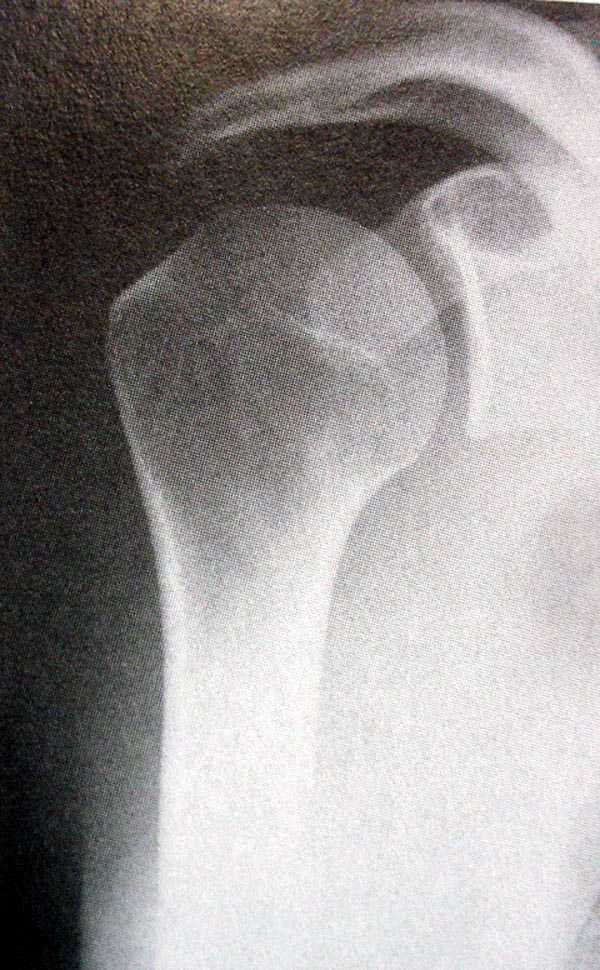

Рентгенологические исследования проксимального отдела плеча состоит из прямого, бокового и аксиальных видов. Если имеются сложные переломы тогда рекомендуется Томография, а так в большинстве случаев достаточно бывает стандартных снимков.

Независимо от условий (нежелание рентгентехника или отсутствие пленок) необходимо добиться рентгенограмм, особенно аксиальной, потому что одна проекция не гарантирует, что не пропущен вывих в плечевом суставе.

На выставленных снимках копии из книги: 1-2 прямая укладка и снимок; 3-3a боковой или Y; 4 аксиальная укладка и снимок.